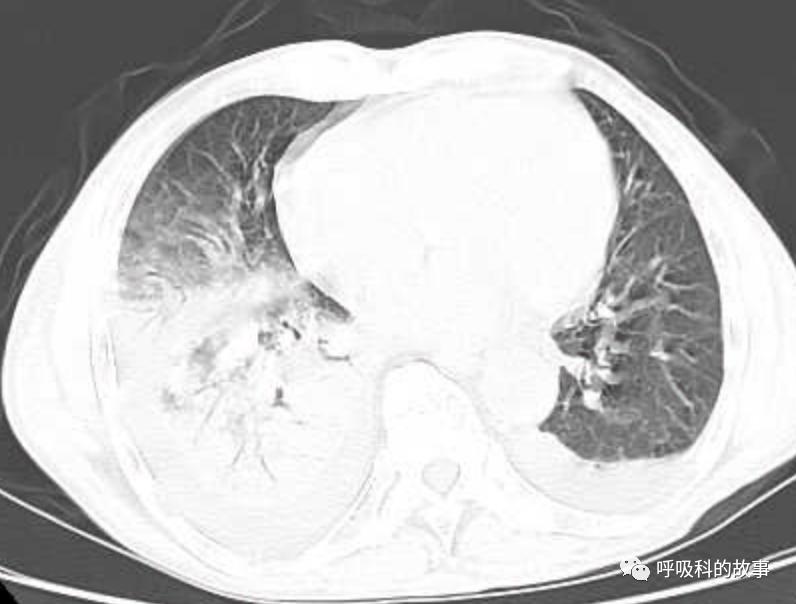

接着,我打开电脑看病历:患者,男,68岁,主诉:发热、头痛伴乏力10余天,咳嗽4天。肺部CT一看是右下叶大片实变肺炎,双侧少量胸腔积液,两上肺内中带片絮状斑片状影。2020.11.30 在外院检查 PCT 7.42ng/ml,ALT 199U/L,AST 250U/L,白蛋白24.7g/L,CRP 108.7mg/L,乳酸脱氢酶LDH388U/L(正常50-240),钾3.27mmol/L;血常规:白细胞4.9*10^9/L,中性85.2%。在外院给予了亚胺培南2天和本院美罗培南治疗2天后,效果并不理想。

(6)肺部影像以大叶性肺炎为主,其他部分是合并肺水肿的影像;